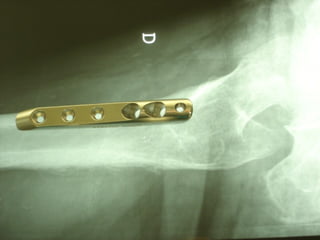

The GOTFRIED plate

La placca a compressione percutanea (PC.C.P.) di Gotfried è un mezzo di sintesi studiato per assicurare un “impattamento controllato” delle fratture pertrocanteriche grazie alle due viti telescopiche prossimali che garantiscono una ottima stabilità rotazionale

Con la placca di Gotfried non si è mai riscontrato un danno iatrogeno del muro laterale e nessun collasso della frattura.Ciò è dovuto al fatto che i fori per l’applicazione delle due viti prossimali sono di piccolo diametro (9 mm) rispetto ai 16-32 mm necessari per introdurre la vite cefalica di un chiodo endomidollare o di una vite-placca a compressione.

La placca PC.C.P. viene inoltre applicata per via percutanea attraverso due piccole incisioni ottenendo in tal modo un minimo trauma chirurgico ed una  perdita di sangue estremamente ridotta in pazienti che per l’età  sono già in condizioni  critiche

Dal Gennaio 2005 ad Agosto 2006 110  placche di Gotfried Età media  : 78 anni (range 29-94) Tempo chirurgico: 30 minuti (range 12-45) IMMEDIATA CONCESSIONE DEL CARICO